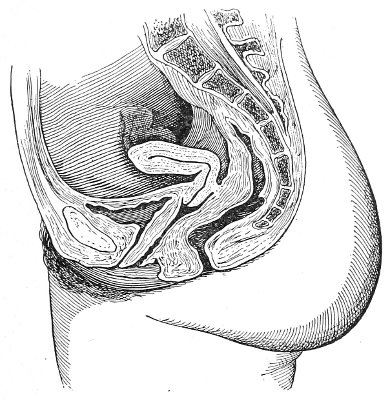

Vaginal and Bimanual Examination.—Having examined and noted the condition of the external genitals, the physician should next proceed to examine the vagina. The index finger of the right or the left hand should be gently introduced into the vagina. The condition of the vaginal walls, and the direction, consistency, form, etc. of the vaginal cervix, may be determined. The shape and size of the os uteri should be noted. The ulnar edge and the tips of the fingers of the other hand should then be placed upon the abdomen, immediately above the symphysis pubis, and gently pressed backward and downward toward the vaginal finger 24 (Fig. 2). In this way the various pelvic organs, the uterus, Fallopian tubes, ovaries, and ureters, may be palpated between the two hands, and their position, size, shape, and consistency may be determined. Such an examination is, of course, made much more easily in a thin woman than in a fat one. A thin woman a few weeks after labor may be examined most easily, on account of the relaxation of the abdominal and vaginal walls.

This is called the bimanual method of examination, and the student will find that as he acquires practice in this method he will gradually depend less upon examination by the uterine sound and the speculum, and will rely altogether upon his sense of touch, his ability to palpate.

In making the bimanual examination the structures 25 should be palpated methodically in order. The vaginal finger notes the condition of the cervix uteri. If the fundus be in the normal position, the uterus can then be taken between the abdominal hand (upon the fundus) and the vaginal finger (upon the cervix) (Fig. 3). The shape, size, mobility, and consistency are noted. The vaginal finger is then passed anteriorly and laterally toward either uterine cornu, while the abdominal fingers pass over to the posterior aspect of the same cornu. The ovarian ligament and the proximal end of the Fallopian tube may thus be felt. Passing farther outward, the whole of the tube and the ovary may be examined. The same procedure is then applied to the opposite side.